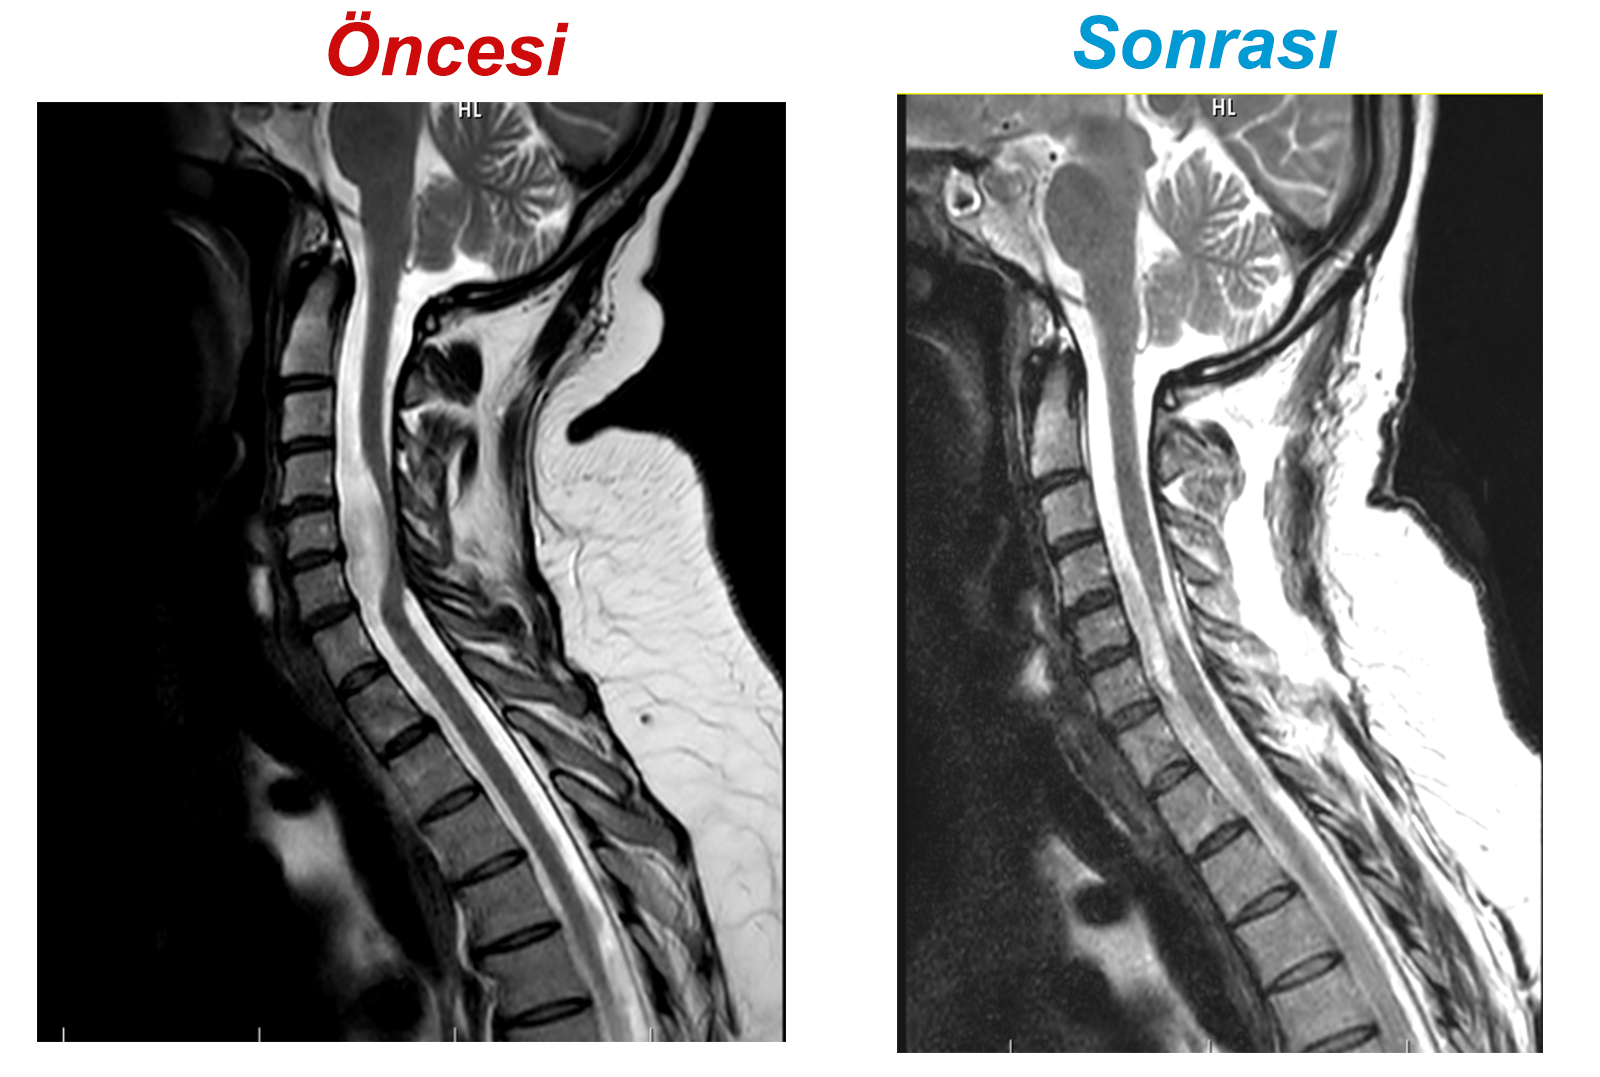

Uzun araştırmalar sonucu Palalı, Kahramanmaraş Sütçü İmam Üniversitesi (KSÜ) Tıp Fakültesi Beyin ve Sinir Cerrahisi Anabilim Dalı Öğretim Üyesi Doç. Dr. İdris Altun'a başvurdu. Altun tarafından yapılan muayene ve tetkiklerde hastanın boyun (servikal) omuriliğinde yerleşimli ve omuriliğe tamamen basan 3,5 cm büyüklüğünde tümör olduğu, kol ve bacaklarındaki güçsüzlük ve kas gücü kaybının tümörden kaynaklandığı tespit edildi. Beyinden çıkarak tüm vücudu kontrol eden ve solunum görevinde etkili olan omuriliğin içinde yerleşimli tümörün çıkarılması için tüm risklerini kabul eden ve doktoruna güvenen hasta, başarılı bir ameliyat geçirdi.

Beyin ve Sinir Cerrahisi Anabilim Dalı Öğretim Üyesi Doç. Dr. İdris Altun, ameliyat hakkında şunları belirtti: “Tümör tüm vücudu kontrol eden, solunum fonksiyonunda etkili olan servikal 4 omurgadan başlayarak 5 omur seviyesinden 6 omura kadar uzanan omurilik içinde yerleşimliydi ve omurilik kanalının ön kısmındaydı. Boyun ön kısımdan çıkarılabilmesi için en az 2 boyun omurga kemiğinin alınması gerekiyordu. Boyun Arka tarafından çıkarılması durumunda omuriliğin zedelenme riski çok yüksek olup felç kalma ihtimali ve hayati risk taşıyordu. Omurgaların çıkarılması, şah damarlar, yemek borusu ve soluk borusunda zedelenmeler ve yaralanmalar olabileceği için arka kısımdan ameliyata karar verildi. Arka kısımdan 3 omurgaya kısmi pencereler açılarak kitleye ulaşıldı. Kolları kontrol eden ve omuriliği besleyen damarların arasından 3,5 cm’lik kitle başarılı bir şekilde tamamen çıkarıldı. Ameliyat sırasında hiçbir komplikasyon olmadı. Ameliyat sonrasında sinir hattı rahatladı. Hastamız gayet iyi ve rahat durumda. Hastamızı bugün de yürüterek taburcu ettik.”